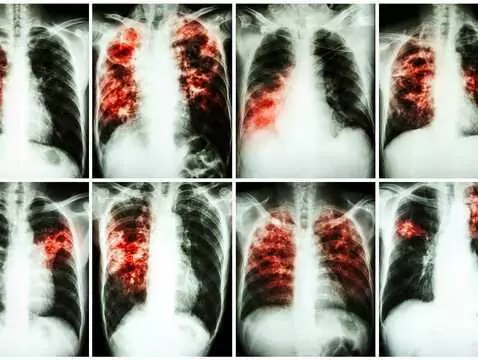

Tuberkulose - eine Krankheit, die nicht verschwunden ist. Am Welttuberkulosetag lohnt es sich, an die wichtigsten Informationen über diese Krankheit zu erinnern.

Es gibt Krankheiten, von denen es heißt, sie seien 'ausgestorben' oder würden nur in Ländern der so genannten Dritten Welt auftreten. Eine solche Krankheit war die Tuberkulose, die als ein...

Forscher der medizinischen Fakultät Hradec Králové der Karlsuniversität in Prag haben ein neues Medikament gegen Tuberkulose erfunden. Das Medikament ist an ein amerikanisches Pharmaunternehmen...